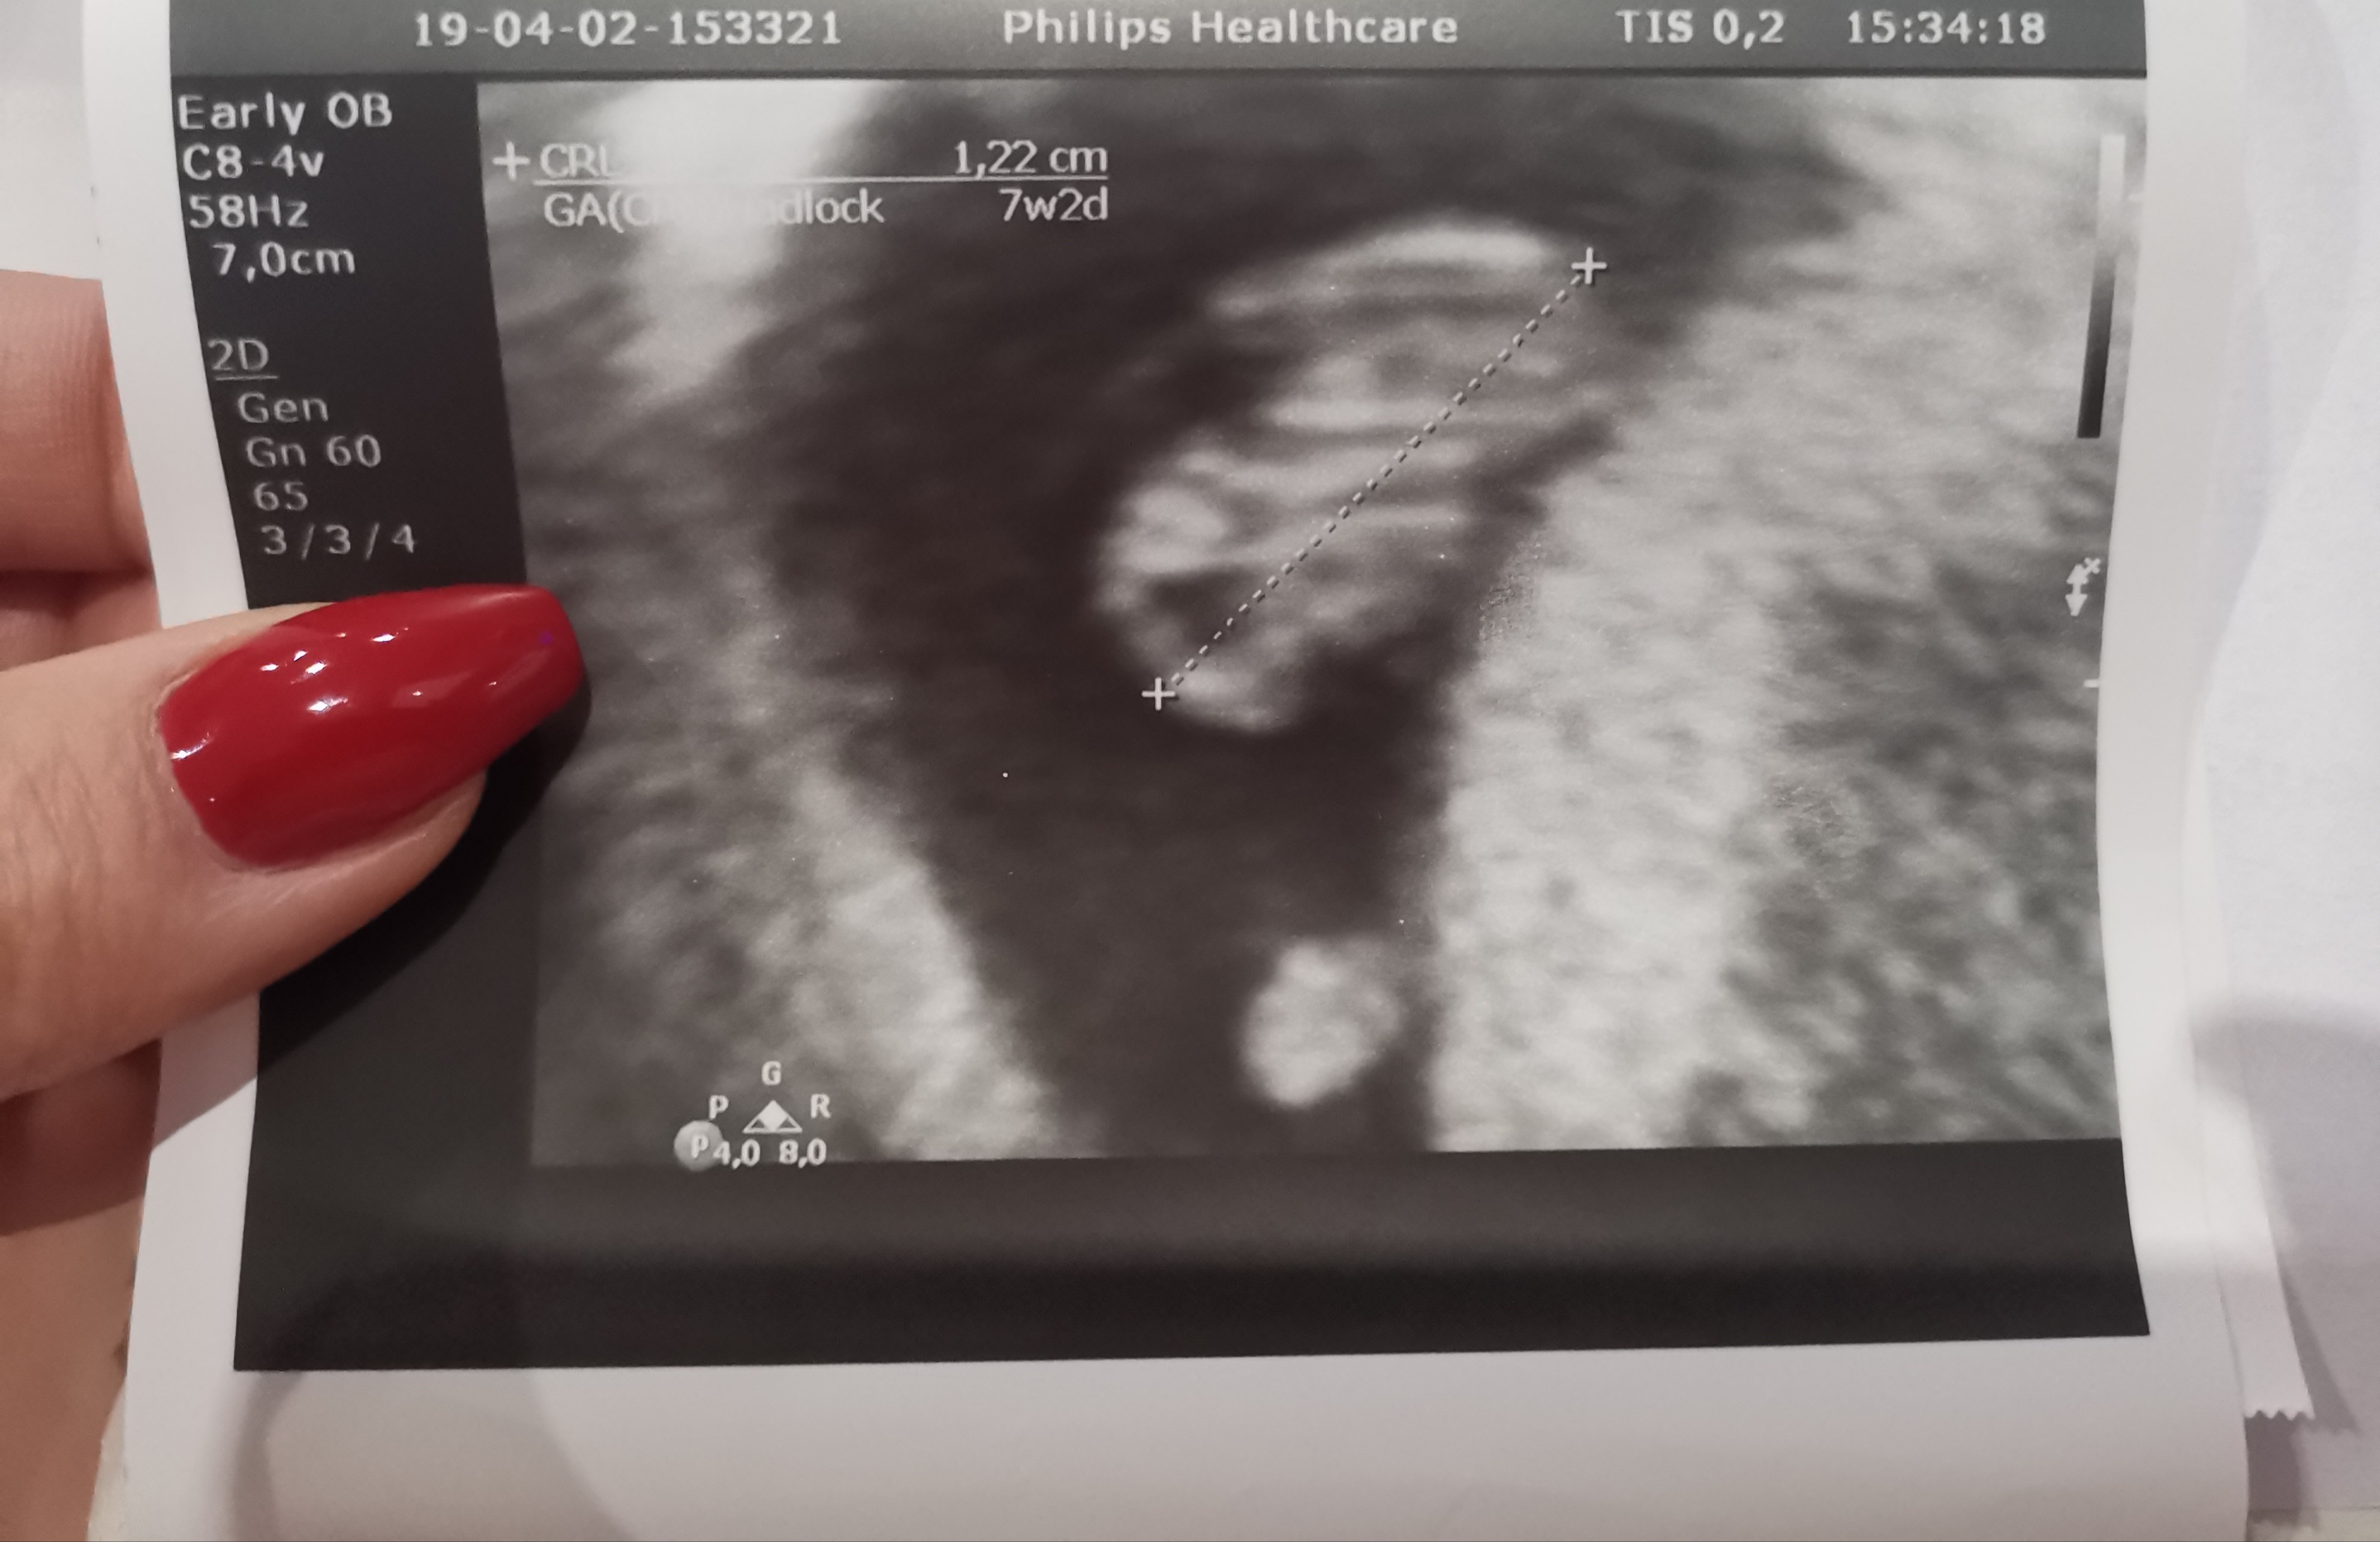

To mój fasolek albo fasolinda. Tak się boję o te małe pikające serduszko... A w pracy do 17 chyba zwariuję :) nie chce mi się siedzieć, chętnie położyłabym się przed telewizor z pizza :p

• IMG_20190403_160253.jpg

IMG_20190403_160253.jpg

876,2 KB · Wyświetleń: 110